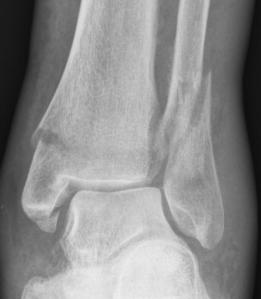

Ankle fractures

Syndesmosis injuries review

Ankle fractures |